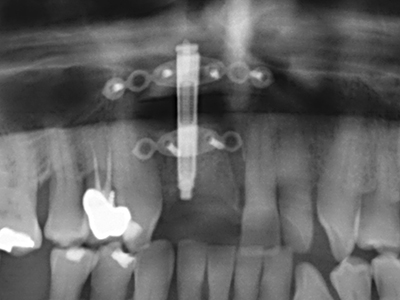

Abb. 11: Das postoperative OPTG veranschaulicht die vertikale Augmentation und Sinusbodenelevation.

Abb. 12: Nach sechs Monaten Heilungsperiode zeigt sich ein in allen Richtungen ausreichend dimensionierter, vitaler Kieferkamm.